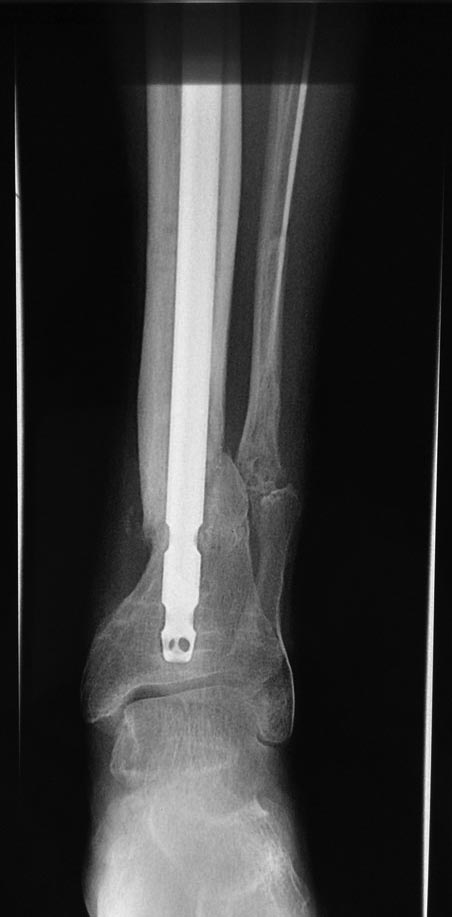

Уважаемые коллеги выразите Ваше мнение по следующему случаю.Молодой человек, 27 лет, находится на лечении с диагнозом: Ложный сустав большеберцовой кости в нижней трети, фиксированный интрамедуллярным блокированным стержнем (12.02.2014 г), ложный сустав малоберцовой кости в нижней трети левой голени, посттравматический артроз левого голеностопного сустава 1 стадии. Укорочение левой нижней конечности на 1,0 см. Со слов пациента известно, что в детстве получил перелом большеберцовой кости, лечился консервативно, перелом сросся с деформацией. Травма в июле 2010 г. бытовая-упал на лестнице, получил перелом малоберцовой кости, и перелом большеберцовой кости без смещения. Выполнена операция: Остеотомия большеберцовой кости в нижней трети, интрамедуллярный блокированный остеосинтез большеберцовой кости левой голени. Гладкое течение послеоперационного периода. Перелом большеберцовой кости сросся. Функция конечности восстановилась. В июне 2013 г выполнена операция удаление интрамедуллярного стержня из большеберцовой кости левой голени. Гладкое течение послеоперационного периода. Приступил к занятием физкультурой, бег. В августе 2013 г спрыгнул с автобуса, с чемоданом в руках, появилась резкая боль в левой голени. За медицинской помощью обратился через 7 дней, при обследовании выявлено: Рефрактура большеберцовой кости. Рекомендовано консервативное лечение в гипсовой повязке. В январе 2014 г. установлен диагноз: Ложный сустав большеберцовой кости в нижней трети, малоберцовой кости в нижней трети левой голени. Контрактура сгибательно - разгибательная левого голеностопного сустава. Посттравматический артроз левого голеностопного сустава 1 стадии. Укорочение левой нижней конечности на 1,0 см. В феврале 2014 г выполнил первым этапом: Фиксацию ложного сустава в АНФ с восстановлением осей сегментов. Через семь дней БИОС с рассверливанием. После операции - вальгус голеностопного сустава. Гладкое течение послеоперационного периода. Нагрузка по переносимости боли. Через 6 недель динамизация, через 2 недели стали мигрировать 2 фронтальных винта. Пытался подкрутить, пришлось удалить. Через 6 мес., контроль - линия ложного сустава прослеживается, но имеется периостальная костная мозоль. Не хватает стабильности.Вопрос что делать?Вариант № 1- выполнить реостеосинтез с рассверливанием КМК и на 12 мм диаметра гвоздь (стоит 11 мм)и убрать ротацию стопы руками одномоментно или одномоментно при помощи АНФ во время операции. Вариант № 2 выполнить удаление гвоздя, сделать все то же, что 6 месяцев назад, но с восстановлением анатомических взаимоотношений в голеностопном суставе.Вариант № 3 Двухэтапно, вторым этапом пластина на большеберцовую кость + костная пластика области не сращения.Вариант № 4 удаление гвоздя и лечение в КДА. Вопросы:1. Какой вариант оперативного лечения будет оптимальным в данном случае.2. При двухэтапной методике в дистальном отломке имеется канал от гвоздя, как направить гвоздь к наружному отделу дистального отломка большеберцовой кости. Есть опасения, что гвоздик может пойти по тому же каналу. Использовать поллер спицы или винты – сработают ли? И достаточна ли будет жесткость фиксации дистального отломка большеберцовой кости на гвоздике при 3 – 4 винтах при реостеосинтезе гвоздем.3. Нужен ли остеосинтез малоберцовой кости в нижней трети, с целью создания латеральной опоры. К сообществу за советом.

Александр Николаевич спасибо за ответ. Три снимка перед внешним видом конечности крайние. На одном из них левая стопа в положении внутренней ротации 15 градусов.